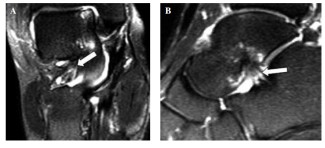

辅助检查:核磁共振MRI必不可少,它可以观察到一些病理改变包括纤维化,弥漫性浸润,非特异性炎症改变,以及异常积液。并发现这些改变与外侧副韧带撕裂之间的相互关系。